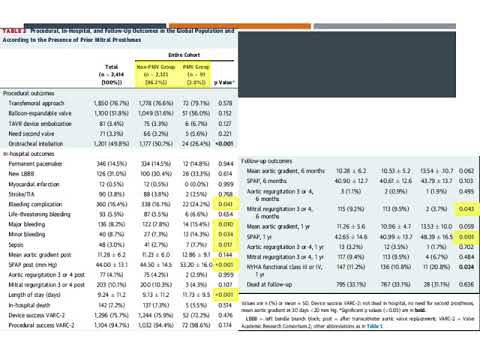

Reparación mitral transcatéter. Dra. Ana Laura Mori. Residencia de Cardiología. Hospital C. Argerich. Buenos Aires